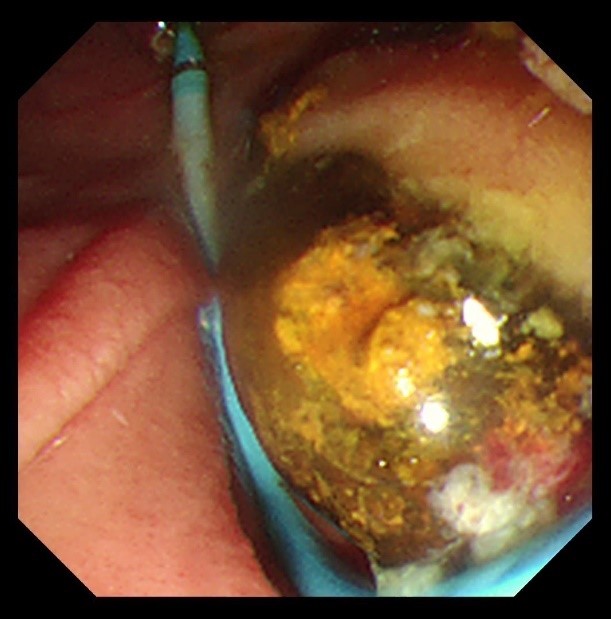

苏大附四院ERCP团队在手术中看到陈大爷的胆总管在结石的影响下已经宽达13mm,结石大小11*10mm,将十二指肠乳头切开并扩张后用取石球囊把结石取出,置入胆管支架使胆汁充分引流,顺利解除了胆道梗阻。

取石前后